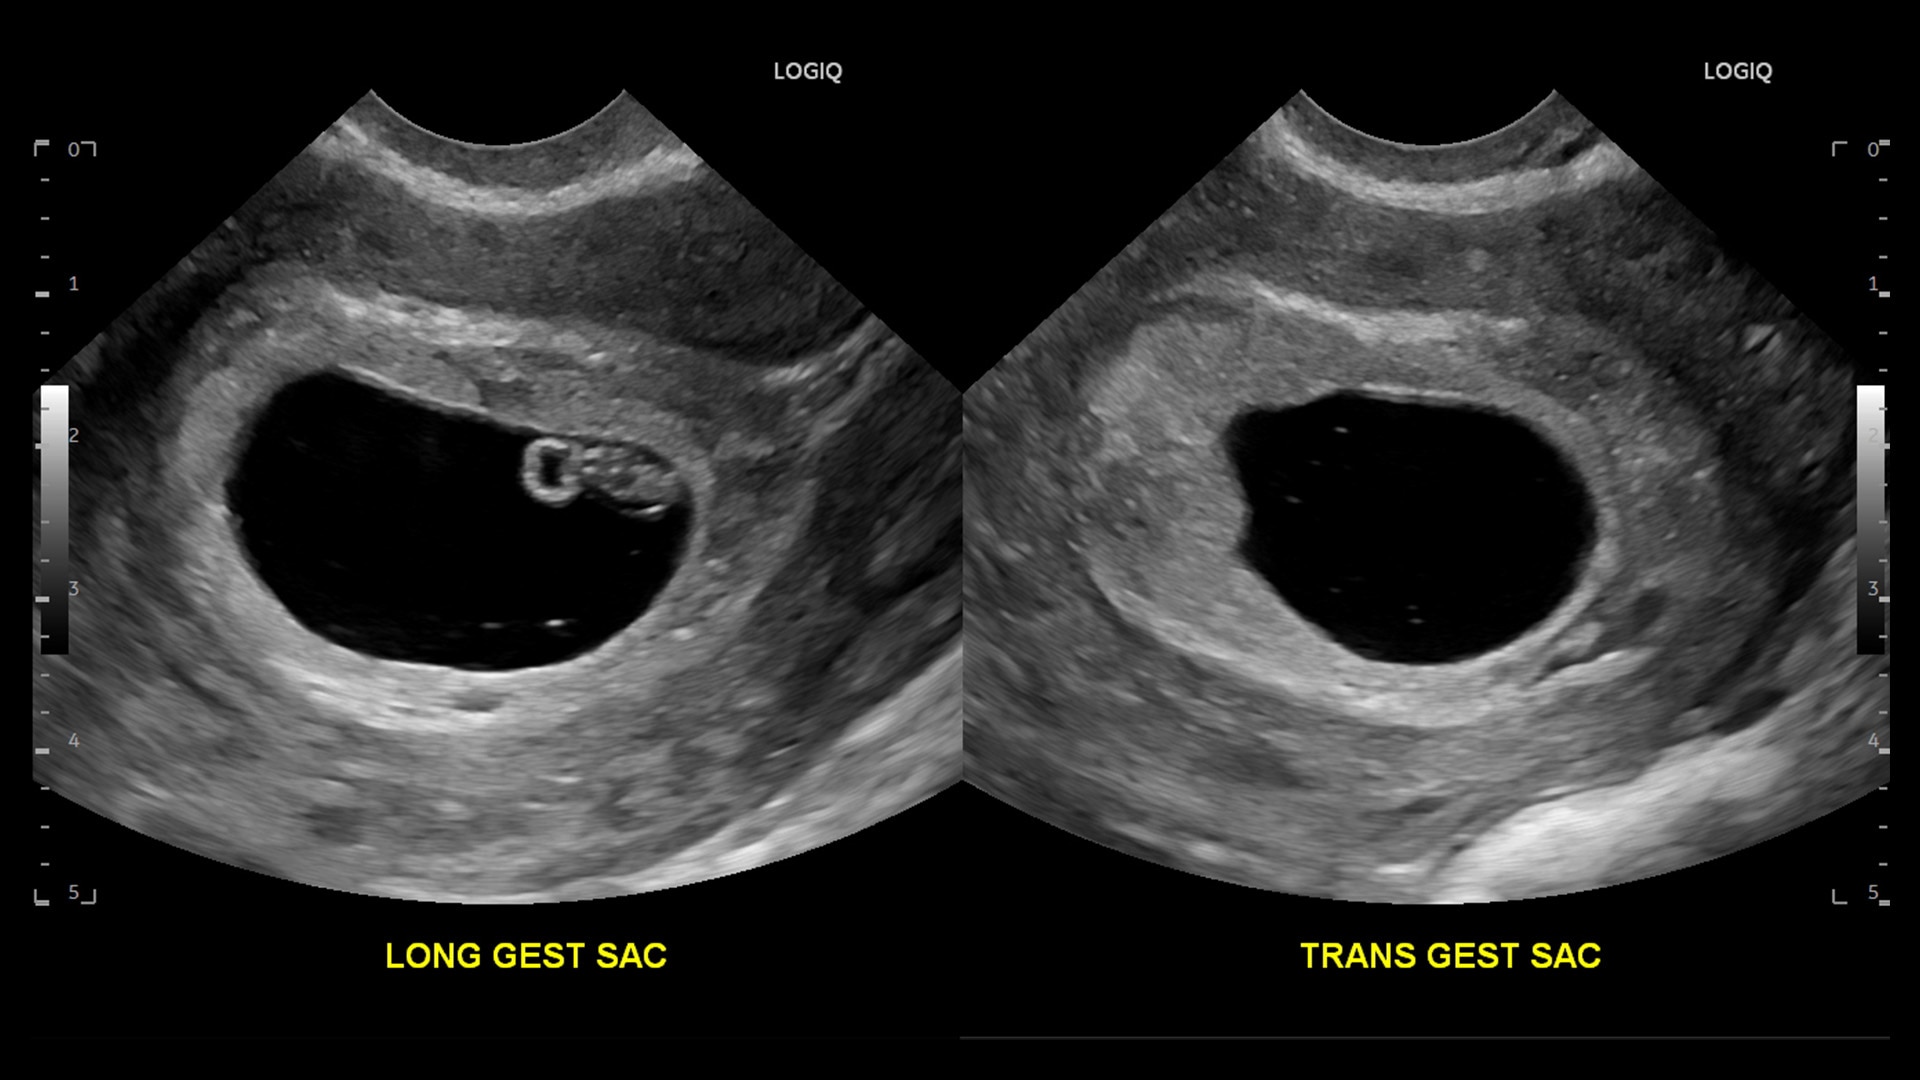

Strength and power to enhance clinical capabilities and deliver exceptional image quality

AI and productivity tools enable new and skilled users to work quickly and manage high-patient volumes